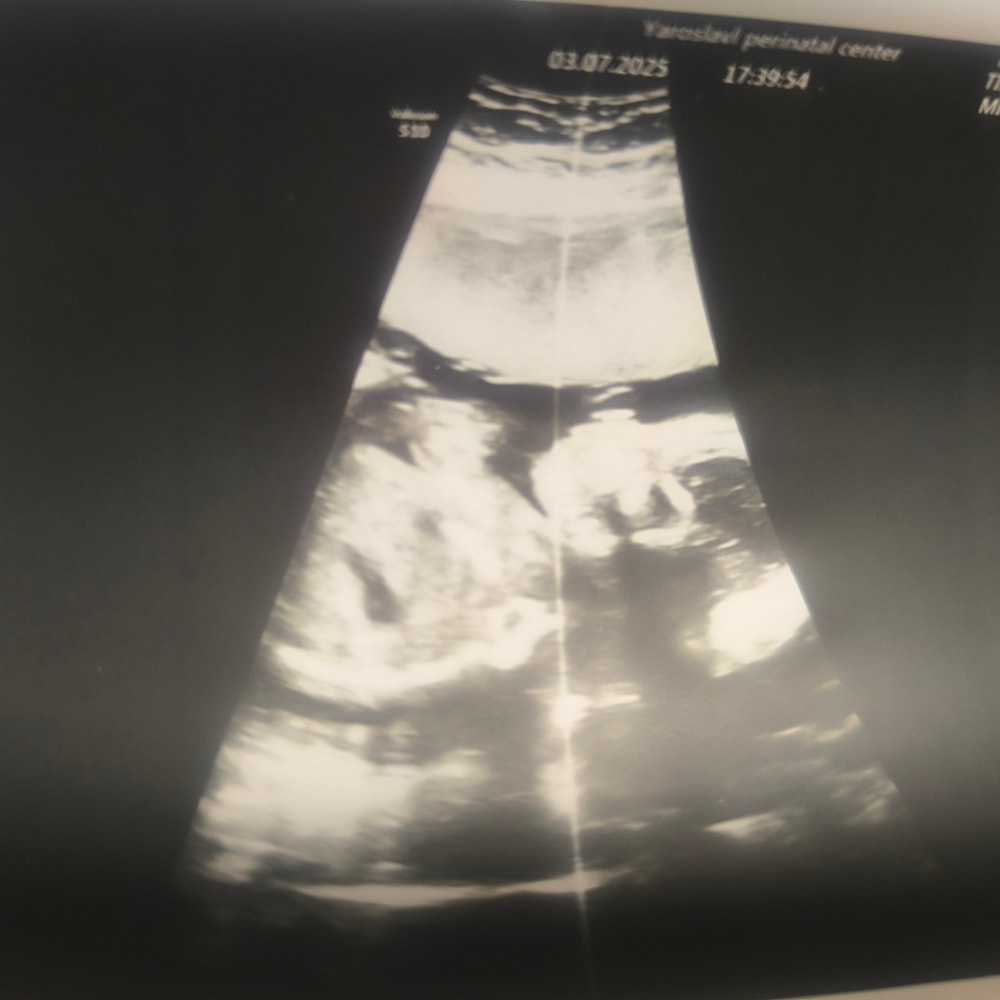

Анализы, скринингиПишу больше для памяти. На сроке 21+2 провели скрининг.

Нам подтвердили девочку 🎀

Сказали длинноногая... Хотя и не в кого вроде 😀 , весит 438 гр уже. Все на месте все в порядке 🙏